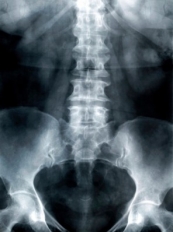

Um hormônio secretado por células ósseas pode suprimir o apetite, de acordo com estudos feitos em camundongos conduzidos por pesquisadores da Columbia University Medical Center (CUMC). O hormônio - chamado lipocalina 2 - ativa neurônios no cérebro os quais foram previamente ligados à supressão do apetite. Os resultados revelam um mecanismo, até agora desconhecido, para o controle do equilíbrio energético do corpo podendo levar a novas terapias direcionadas para o tratamento da obesidade, diabetes tipo 2 e outros distúrbios metabólicos.

Em 2007, uma equipe do CUMC liderada por Gerard Karsenty, MD, PhD, professor de Genética e Desenvolvimento na Paul A. Marks e professor de medicina, e presidente do Departamento de Genética e Desenvolvimento da CUMC, foi o primeiro a descobrir que o osso é um Órgão endócrino que regula o metabolismo energético através da liberação de um hormônio chamado osteocalcina. "Nós hipotetizamos que haviam hormônios ósseos adicionais que regulavam o metabolismo, uma vez que outros órgãos endócrinos que afetam o metabolismo costumam fazê-lo através de múltiplos hormônios", disse o Dr. Kousteni.

No presente estudo, os pesquisadores do CUMC demonstraram que os osteoblastos deficientes em FOXO1 expressam quantidades estranhamente elevadas de uma proteína chamada lipocalina 2. Anteriormente, pensava-se que a lipocalina 2 era essencialmente secretada por adipócitos (células de gordura) e contribuía para a obesidade. Mas os pesquisadores mostraram, através de camundongos que não produziam lipocalina em suas células de gordura ou osteoblastos, que a lipocalina 2 é principalmente secretada pelos osteoblastos e reduz o apetite e o peso.